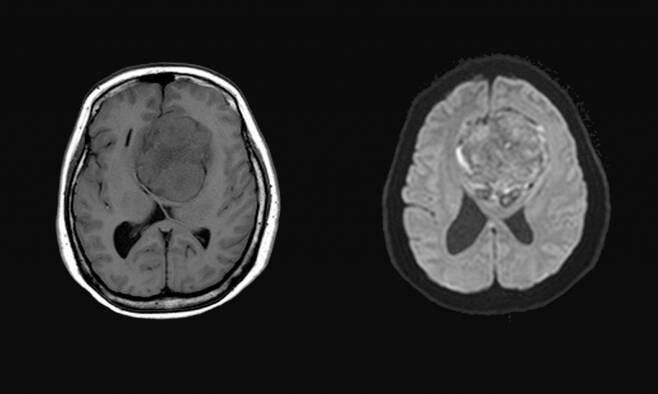

아울러 복지부는 하반기부터 뇌·뇌혈관 MRI를 의학적 필요성이 분명한 경우에만 급여로 보장하기로 했다. 일부 의료기관에서 뇌 질환과 무관한 단순 두통·어지럼에 대해 건강보험 급여를 청구하는 경향이 늘어서다.

이에 복지부는 뇌·뇌혈관, 두경부 MRI 검사 건강보험 급여 적용 기준을 명확화했다. MRI 검사가 필수적인 두통·어지럼, 특발성 돌발성 난청 등 해당 여부를 명확히 판단할 수 있도록 급여기준을 구체화했다. 군발두통 급여 인정 위해서는 '특징적인 신경학적 이상 증상' 충족이 필요하다.

고령, 고혈압, 흡연 등 요인을 가진 환자에서 발생한 두통, 어지럼 등은 의학적으로 뇌질환 연관성이 낮은 것으로 보고 급여 대상에서 제외하기로 했다.

또 두통·어지럼 복합촬영 급여 보장 범위는 최대 3촬영에서 2촬영으로 축소한다. 다만 벼락두통 등 중증 뇌질환이 우려되어 의학적으로 3촬영이 필요하다고 판단되는 경우에는 진료기록부에 사유를 명확히 기재한 경우에 한해 예외적으로 허용한다.

부적정 검사 빈발 기관에 대한 심사는 강화한다. 구체화된 급여 기준을 토대로 급여 청구 데이터 분석을 통해 의학적 필요성이 낮은 MRI 검사 빈발 시행 기관을 선별, 집중 심사한다.